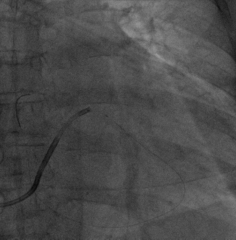

固定左室电极,连接CRTD(DTBC2QQ),手术最终影像

在缝合过程中即由工程师进行无线测试(可不通过程控探头探寻)

如上图,通过Vector Express功能很快自动测试四极多向量的阈值供参考,选择LV2-LV3向量,该向量阈值最低,预估寿命最长

心房、右室、左室的其它参数也均满意